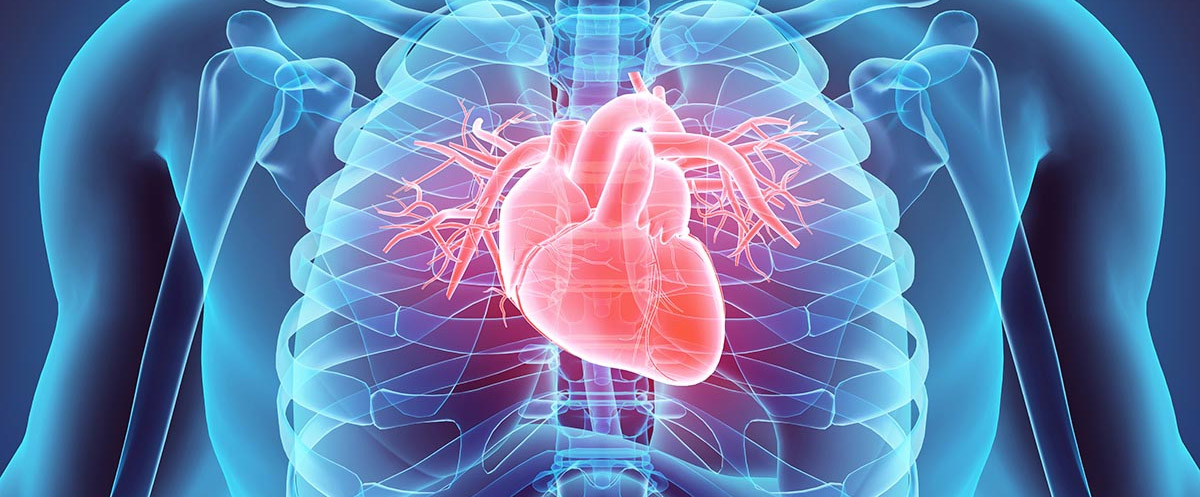

DETAYLI BİLGİCheck up, günümüzde sağlıklı bir bireyin, olası sağlık sorunlarının ve hastalıklarının önceden tespit edilmesi için yapılan sağlık taramasıdır.

Check-up ile ERKEN TEŞHİS mümkündür.

Kardiyak MRI doğumdan gelen kalbe ait hastalıkları, kalp boşlukları ile kalbe giren ve çıkan ana damar yapılarının değerlendirilmesi ve fonksiyonları bakımından çok önemli bilgiler sağlamaktadır.